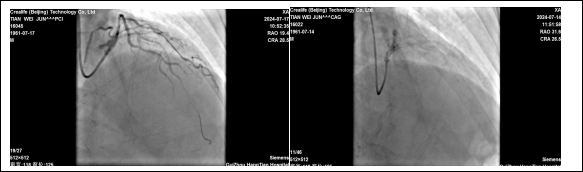

贵州航天医院心血管内科 应用国产冲击波球囊系统 完成严重钙化病变手术 近日,我院心血管内科团队成功为一名急性心肌梗死合并冠脉重度钙化患者实施了“冲击波球囊术”。手术取得了显著效果,术后患者症状明显改善。 63岁田先生,因胸痛2小时就诊我院心血管内科,经冠脉造影检查,提示:冠脉前降支的近中段弥漫性狭窄约80%-95%,局部明显“钙化影”。血管内的钙化病变就是导致患者胸痛的根本原因。 术前:前降支冠脉弥重度狭窄,伴钙化。 术中:冲击波球囊释放脉充、扩张。 心血管内科姜黔锋团队经过认真研究病情、冠脉造影图像,考虑到老年患者冠状动脉钙化重、血管迂曲的情况,进行常规冠脉旋磨风险大,单纯球囊扩张,难以取得满意的效果,在衡量多种手术方案,取得患者及家人同意后,决定采用血管内冲击波球囊治疗技术进行治疗,重点解决因冠脉重度环形钙化,直接支架植入贴壁不良,支架内在狭窄,急性血栓形成影响远期预后等的问题。 术后:支架植入后,血管畅通,效果良好。 针对此情况,由沈万贵主任担任术者,通过双导丝、预扩张球囊等进行预处理后,精准将冲击波球囊送至病变处,经释放脉冲后,OCT(经光学相干断层扫描的冠状动脉血管内影像)证实钙化病变已经完全打开,后扩张球囊充分扩张钙化病变处,很快达到了理想的手术条件,顺利完成支架植入。术后患者血管狭窄消失,血流通畅,胸闷、胸痛症状明显缓解,达到了预期的治疗效果。 我院心血管内科首次应用国产冠脉冲击波治疗系统完成手术,凭借丰富的手术经验和技巧,助力患者重获新生,标志着我院心血管内科冠脉血管钙化病变介入治疗技术再上新台阶,将为更多复杂、严重冠脉钙化患者带来“心”希望。未来,心血管内科团队将继续开拓进取,紧跟学科前沿,积极应对人口老龄化、心血管疾病复杂化,努力为患者提供规范、高质量的医疗诊疗技术服务。 延伸阅读 01 什么是冲击波球囊技术? 冲击波球囊技术,或称血管内碎石术,源自泌尿系统结石治疗的碎石原理,经过结合球囊成形技术的创新发展,成为一项新的治疗技术。 采用声压力波有针对性地作用于冠状动脉内膜及中膜下的钙化病灶,在不影响血管内膜完整性的情况下,有效地震松或震裂钙化病灶,恢复血管顺应性,为后续冠脉支架的植入提供更理想的管腔。 02 冲击波球囊技术的优势? 1.能够在不损伤血管壁的情况下,有效碎裂钙化物质,提高血管顺应性,为后续的支架植入手术创造更好的条件; 2.术中血管夹层、穿孔、远端栓塞、慢血流、无复流等并发症风险显著降低; 3.操作简便、安全性高、疗效显著; 4.是目前唯一能够有效处理浅层和深层钙化的技术。 贵州航天医院心血管内科简介 贵州航天医院心血管内科是遵义市市级重点专科,遵义市远程心电示范中心,遵义市高血压慢病管理示范中心。近年来成功获得胸痛中心标准版、房颤中心标准版,儿童先天性心脏病定点救治单位授牌,编制床位60张,科室配置了29台24小时动态心电图、110台24小时动态血压、心脏除颤仪、监护仪、输液泵、微量注射液,同步12导联、18导联心电图机、临时心脏起搏器、床旁血糖仪、主动脉内球囊反搏、食道超声、血管内超声诊断仪及DSA心血管诊疗等。 开展了急诊冠脉介入诊疗,冠脉复杂病变介入术、冠状动脉斑块旋磨术、心脏再同步治疗起搏器植入术、心脏再同步治疗除颤器植入术、射频消融术【心房颤动(导管消融、冷冻消融)、心房扑动、房性心动过速、室性心动过速、室性早搏】、结构性心脏病介入治疗【房间隔缺损(卵圆孔未闭)封堵术、室间隔缺损封堵术、动脉导管未闭封堵术、冠状动脉瘘封堵术、左心耳封堵术等】、临时起搏器植入术、常规永久起搏器植入术(双腔、单腔)、下肢动静脉造影术、下腔静脉滤器植入及取出术、自主肾上腺静脉采血、颈动脉支架植入术、外周动脉支架植入术、肾动脉支架植入术等,积极开展冠脉内超声检查、FFR、OCT、心脏射频三维手术,同时开展了房颤一站式治疗(房颤射频消融术+左心耳封堵术)、主动脉瓣介入术等,在外院专家指导下完成腹主动脉支架植入术。 心血管内科门诊时间及地点 心内科门诊地点及就诊时间 门诊一楼012/013诊室 周一至周五(08:00-17:00) 周六、周日及节假日(08:00-16:00) 心内科咨询电话 一、病房护士站:0851-28611793(外科综合楼9楼) 二、医生办公室:0851-27677832 三、心内科门诊:0851-28614631 四、心内科总值班电话:17785233019 科室专家 注:部分图片来源于网络,如有侵权,请联系删除。 精彩推荐 供 稿:曹昌强(心血管内科) 编 辑:唐语蔚 一 审:沈万贵(心血管内科) 二 审:陈 伟 三 审:蒙昌耀